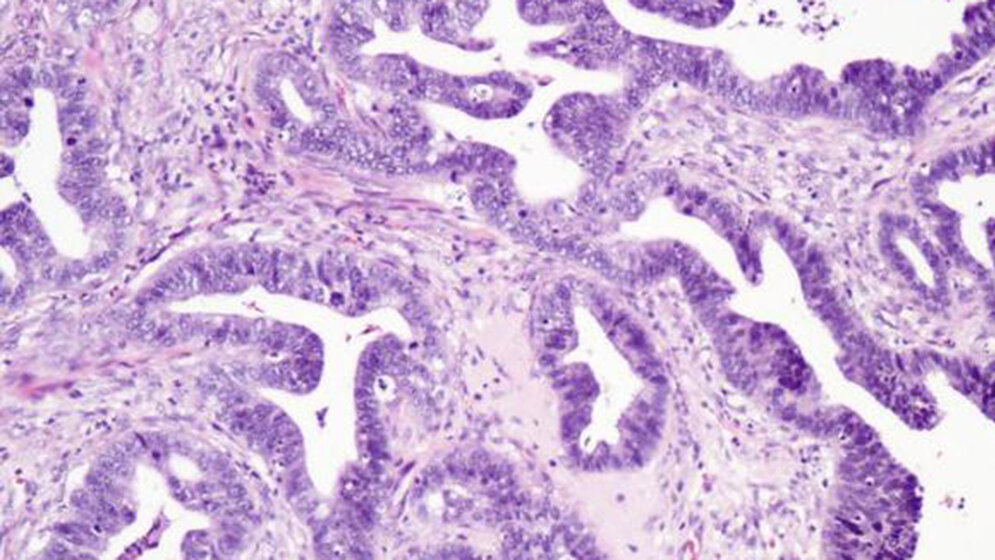

Der Gynäkologe legt durch ein Spekulum den Zugang zur Vagina, Portio und zum Zervixkanal frei. Danach streicht er mit einem Bürstchen oder Spatel über die Transformationszone der Cervix uteri und entnimmt dabei Zellproben, welche er auf einen Objektträger ausstreicht und anschließend sofort mittels Fixierlösung feuchtfixiert. Diese Proben werden an ein Labor geschickt, dort werden sie gefärbt und eingedeckt und anschließend unter dem Mikroskop auf Zellveränderungen untersucht.